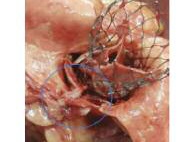

В ходе патологоанатомического вскрытия обнаружена тотальная обструкция устья ЛКА флотирующим фрагментом левой коронарной створки нативного АК (рис. 10). Гистологическое исследование препаратов ЛЖ подтвердило наличие зон острой ишемии и некротических изменений миокарда различной давности (до 24 ч).

Рис. 10. Самораскрывающийся биопротез в аортальной позиции. Синим цветом обведен фрагмент расщепленной левой коронарной створки нативного АК, обтурирующий устье ЛКА.